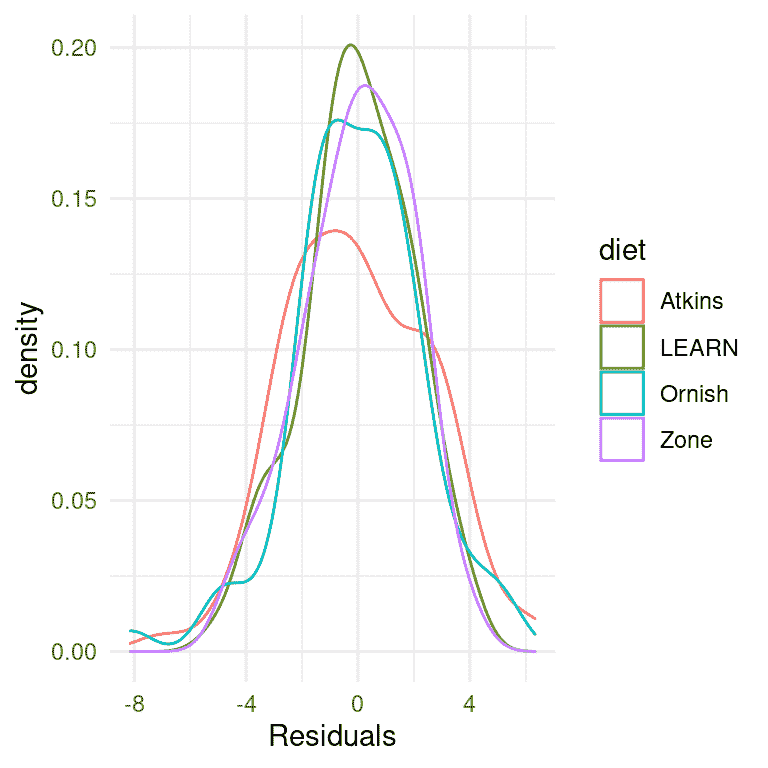

我们首先要做的是批评模型,确保它是适当的。我们可以做的一件事是查看模型的残差。在图 17.2 中,我们按饮食对每个个体的残差进行了绘制。在不同条件下残差的分布没有明显的差异,我们可以继续进行分析。

图 17.2: 每个条件下残差的分布